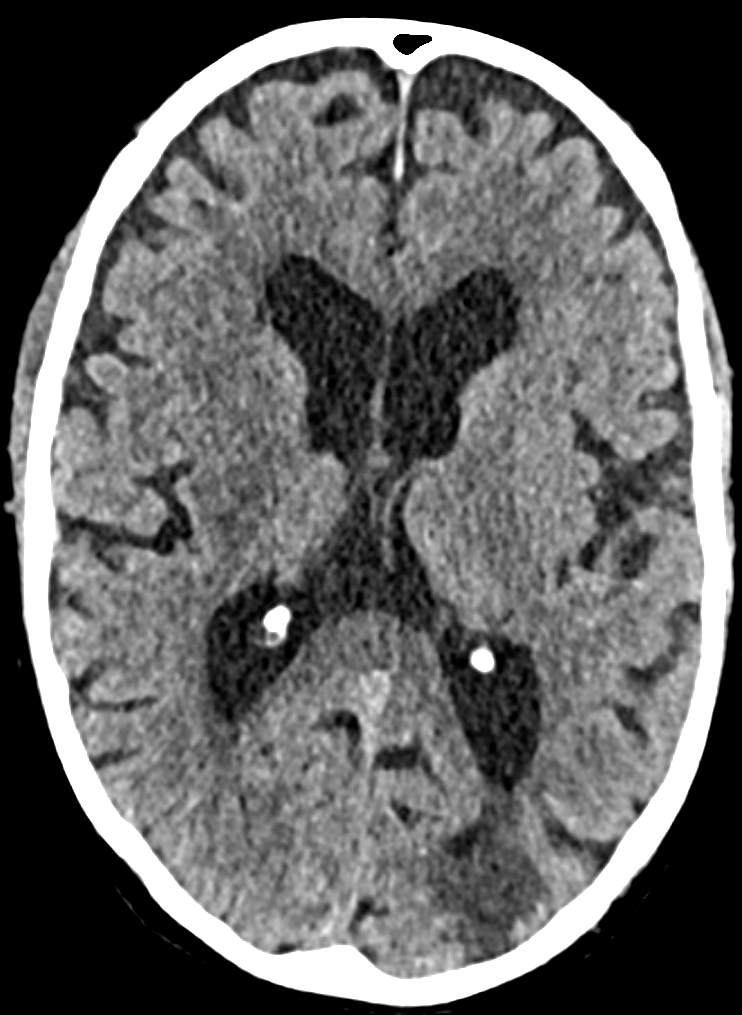

Left parietal lobe infarction